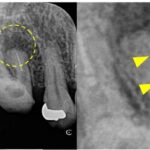

左上の第一小臼歯(4番)には虫歯が認められ、レントゲン・CTにて明瞭な骨吸収像が認められました。痛みなどの症状はないものの、このまま被せ物の治療をやりかえる場合、将来的に根の先の膿が大きくなる可能性があるため、根管治療が第一選択であるとお伝えし、根管治療を開始することになりました。

治療後6ヶ月で根尖部の透過像は縮小傾向を認め経過良好のため、ジルコニアクラウンによる最終補綴治療へ移行しました。

術後24ヶ月が経過時点でのCT画像では、もともとはっきりと写っていた根の先の黒い部分は完全に消失し、骨の回復が認められます。被せ物の適合にも問題なく、良好な経過をたどっています。